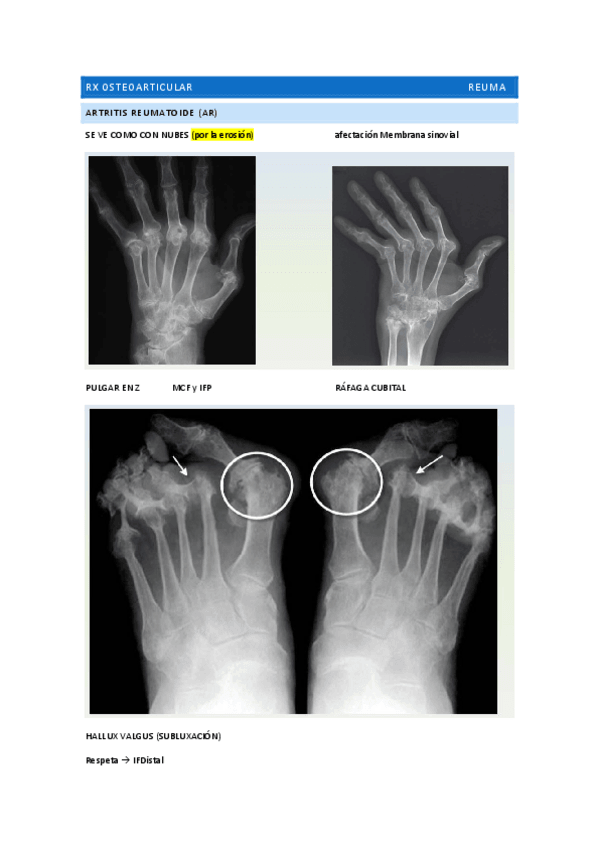

He publicado nuevos apuntes de 2º Cuidados de Enfermería en Procesos Osteoarticulares: RXs-REUMA-POWERS.pdf

7 páginas